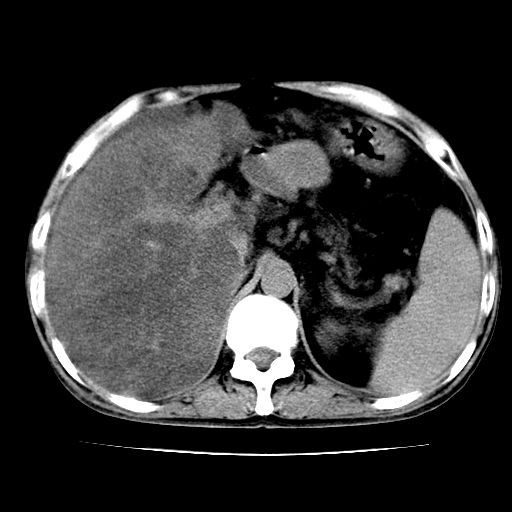

男,55岁,发现“肝硬化”5年,现腰疼、腹胀10余日,巩膜黄染、腹稍胀,肝肋下3指,质硬无压疼,移动性+,血生化:总胆、直胆、间胆均升高。

g1:肝硬化、脾大、腹水。

2:脂肪肝。

3:弥漫性肝癌待排。

肝硬化,脾大,腹水

脂肪肝

肝内多发低密度灶(建议增强扫描除外肝癌)